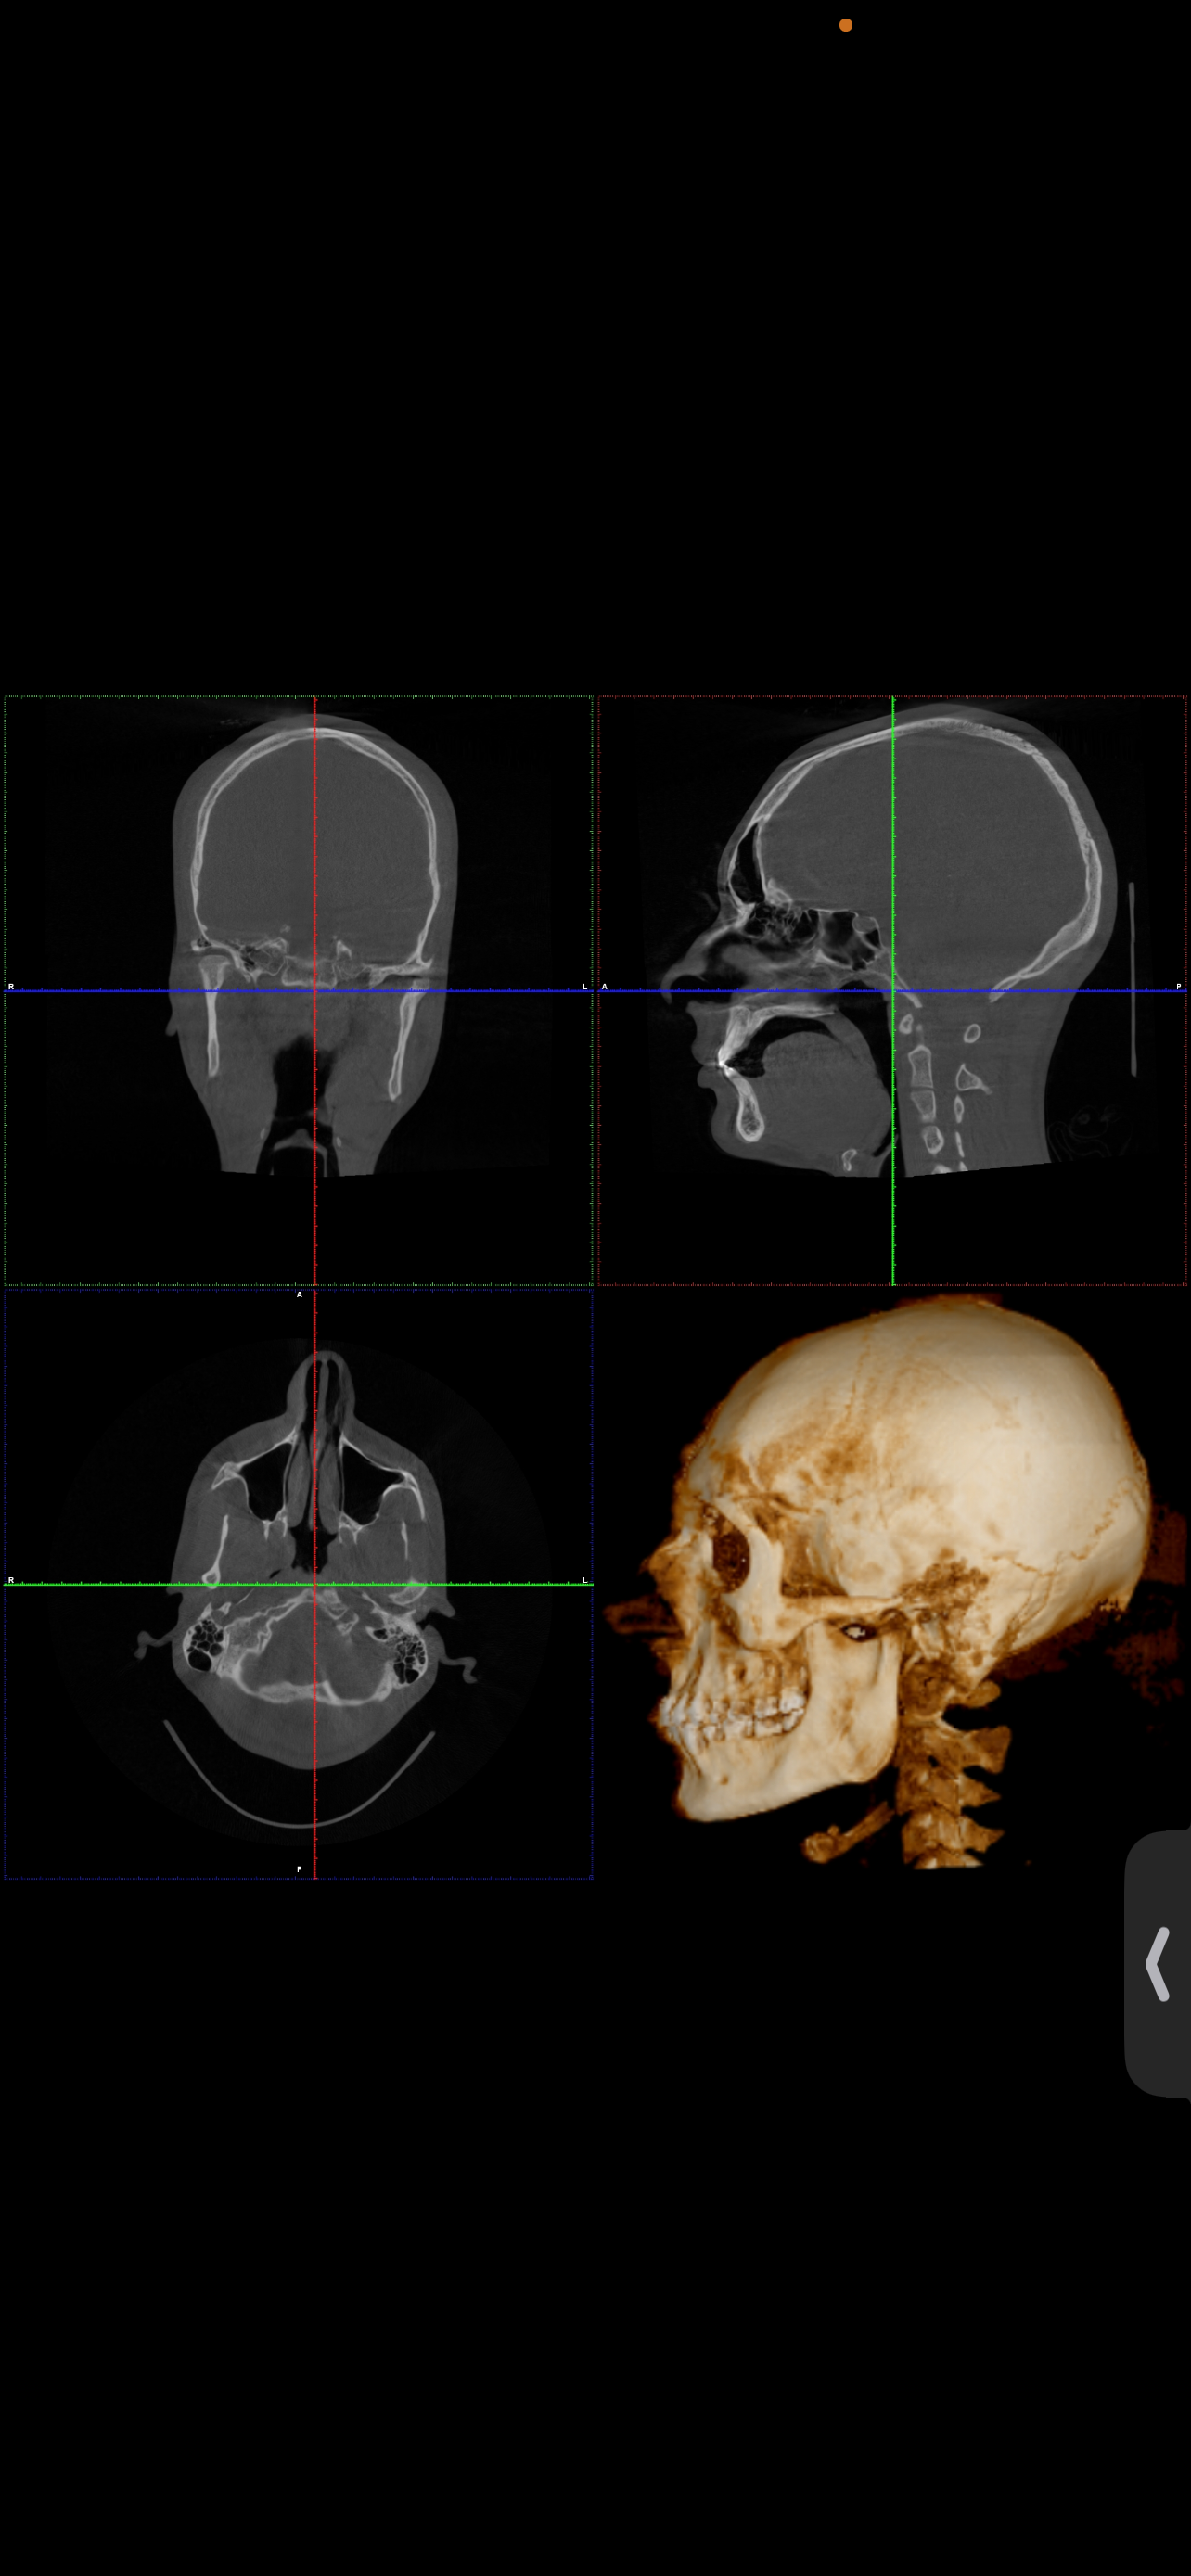

Ct scan for reference

Your mandible is recessed and your airway oropharynx cross section looks very small. Just imagine when you relax and lay down, your tongue goes back and blocks your airway even more.

Get a sleep study (preferably type 1 or 2, type 3 is bad) and consult a maxillofacial surgeon

The philtrum seems quite tall in the ct which may explain why your teeth show less. You have room for advancement in both jaws